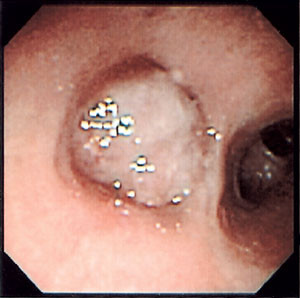

For en del pasienter er alternativet til endobronkialt inngrep en større kirurgisk operasjon. Selv etter tidligere trakeal reseksjon har behandling med trakeal stent vært nødvendig. Figur 1 viser en pasient med følgetilstand etter trakeostomi ti år tidligere. Etter stentbehandlingen ble pusten bedret betydelig (fig 2).

Karsinoider utgjør bare ca. 1 % av lungesvulstene, og en del av dem opptrer nærmest som benigne svulster (5). I fireårsperioden er det behandlet åtte pasienter med karsinoid, i alt 11 behandlinger. To av disse fikk palliativ behandling, men hos seks pasienter hadde behandlingen kurativt siktemål (fig 3, fig 4). En pasient måtte henvises til lobektomi fordi svulsten hadde spredt seg utenfor bronchus. Hos fem synes behandlingen å ha ført til helbredelse, men observasjonstiden er ennå for kort for enkelte til at det kan slås fast. Det er lansert et eget sett forutsetninger for at laserbehandling skal være aktuelt ved karsinoider (6). Det må foreligge såkalt typisk karsinoid histologisk, og det må vokse endobronkialt, det vil si at CT-undersøkelse ikke skal vise svulstvev utenfor bronchus. Disse pasientene slipper altså torakotomi. Ved vanlig kirurgisk behandling vil resultatet ofte være at pasienten mister en eller to lapper, slik norske materialer viser (7, 8).